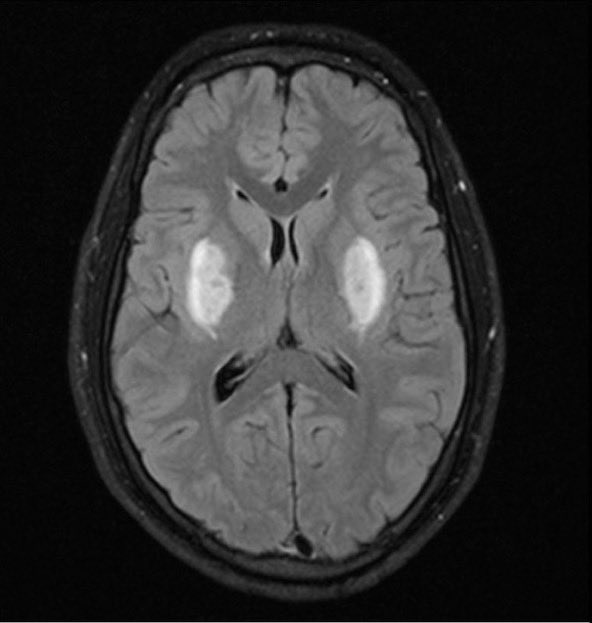

@alhasandr1 @MattersoftheH14 @ED_Ultrasounder @doctor_roig @EM_RESUS @smithECGBlog @ECGfan @rob_buttner @EkgHacks @ecgrhythms @OnlyEcg1 @CardiacPA1 @ekgdx @TheEKGGuy @BrooksWalsh Terminal R in AVR with RS ratio greater than 0.7…wide complex, could it possibly be due to TCA OD?